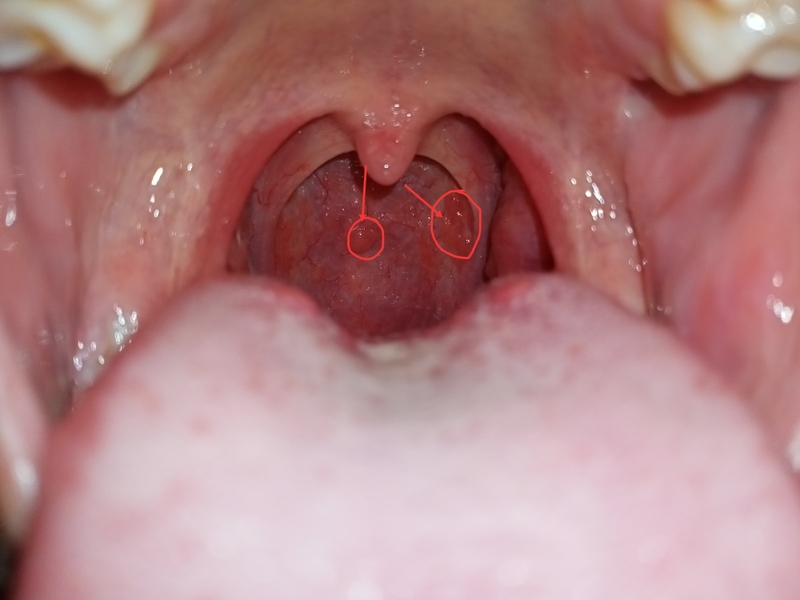

Khi bạn phát hiện có những hạt màu trắng nhỏ trong cổ họng, giống như hạt gạo, và bạn cảm thấy ngứa ngáy, đau rát và khó nuốt, đó có thể là dấu hiệu của một số vấn đề về vòm họng. Theo các chuyên gia y tế, những hiện tượng này có thể là cảnh báo về các bệnh lý sau đây với mức độ nguy hiểm khác nhau:

Viêm họng hạt là một triệu chứng phổ biến nhất và thường gặp khi có hạt nổi trong vòm họng. Khi bạn bị viêm họng hạt, vòm họng bị tổn thương và gây ra ngứa rát, đau cộm và khó chịu khi ăn uống, nuốt và thậm chí khi nói chuyện.

Hiện tượng có hạt nổi trong vòm họng cũng có thể là dấu hiệu của viêm amidan, một căn bệnh phổ biến mà hầu như tất cả trẻ em ít nhất một lần gặp phải trong đời. Đối với các bậc cha mẹ, không cần quá lo lắng khi phát hiện những biểu hiện không bình thường trong cổ họng của con. Hãy điều chỉnh tinh thần và đưa con đến bệnh viện để được bác sĩ kiểm tra và điều trị.

Khi amidan bị viêm, có thể xuất hiện mưng mủ và gây sưng phù, đau rát, gây khó khăn trong việc ăn uống và nói chuyện. Do đó, nhanh chóng đến các cơ sở y tế để kiểm tra và điều trị. Nếu không được điều trị kịp thời, tình trạng này có thể dẫn đến viêm amidan mủ nặng và nguy hiểm.

Ung thư vòm họng là một căn bệnh nguy hiểm mà ban đầu không có triệu chứng rõ ràng, dễ bị nhầm lẫn với các vấn đề thông thường về họng, khiến người bệnh thường có quan niệm chủ quan. Các triệu chứng của bệnh ung thư vòm họng bao gồm: Có hạt nổi trong vòm họng, đau rát cổ họng, sưng tấy vòm họng, vòm họng chảy mủ và máu, cùng với tình trạng suy nhược cơ thể và đau rát nghiêm trọng trong vòm họng.